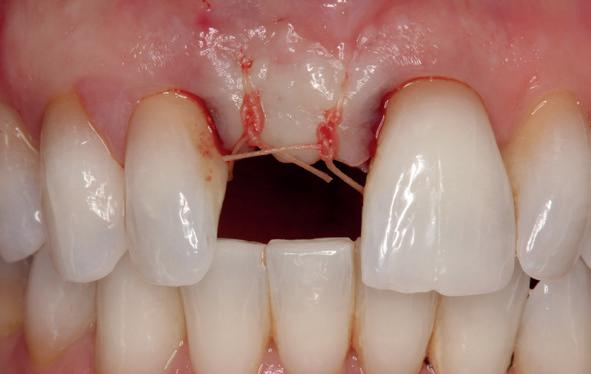

Lateraal van de implantaten wordt de kaak fors uitgebouwd volgens de Hybride GBR-techniek met Oragraft (allograft) van Lifenet die wordt vermengd tot een cocktail met BioOss (xenograft) van Geistlich, autoloog geoogste botsnippers en verzameld bloed uit het wondgebied. De botgraft wordt bedekt met een Ossix (crossed linked) membraan en met Hyadent (hyaluronzuur) overspoten. De sinuslift wordt gelijktijdig met de laterale botopbouw volgens de Caldwell Luc methode uitgevoerd en de uitgeprepareerde holte opgevuld met de botgraft. De flaps worden eerst horizontaal ontlast (gemobiliseerd) en vervolgens naar elkaar toe gehecht met vicryl rapide. Daarbij wordt gebruikgemaakt van horizontale matrassen, zodat de wondranden passief tegen elkaar

komen te liggen en de flaps primair gesloten kunnen worden. Het passief sluiten van een flap voorkomt wonddehiscenties in de genezingsfase die als complicaties kunnen optreden en botregeneratie verstoren. Daarnaast wordt bij een wonddehiscentie het risico op infectie van de graft sterk verhoogd waardoor het gewenste resultaat niet kan worden bereikt. Afstoting van graft materiaal komt dan veelvuldig voor soms gecombineerd met abcesvorming als geen voorzorgsmaatregelen worden genomen. Complicaties moeten daarom nauwlettend gevolgd worden totdat ze verdwenen zijn. De patiënt krijgt na chirurgie postoperatieve instructies en adviezen over de postoperatieve zorg. Daarbij wordt ook de nadruk gelegd op het koelen (coldpack) en zijdelingse druk op de wang. Het blijkt dat koelen en het uitoefenen van druk op het operatiegebied oedeem en hematoomvorming grotendeels kunnen verminderen en soms zelfs kunnen voorkomen.

Twee weken later zie ik de patiënt terug voor controle van de eerste wondgenezing. De noodprothese mag de eerste twee weken niet gedragen worden en wordt tijdens de controle zorgvuldig aangepast aan de nieuwe situatie. Hiervoor wordt de prothese gedeeltelijk uitgefreesd en voorzien van een Soft Reliner materiaal. Te veel druk op de beide kaken moet ten alle tijden voorkomen worden en heeft effect op de ingroei van de botopbouw. De genezingsperiode duurt tenminste zes maanden voordat verdergegaan kan worden met de tweede fase: de abutment chirurgie. Hierbij wordt extra aandacht besteed aan het herstel van de gekeratiniseerde gingiva rondom de abutments. Dit komt ten goede aan de uitvoering van de mondhygiëne en dus de stabiliteit van de peri-implantaire mucosa. Deze ogenschijnlijk eenvoudige behandeling is essentieel voor de prognose van de implantaten op de lange termijn. Te weinig gekeratiniseerde mucosa maakt zelfzorg (borstelen/interdentaal reinigen) vaker pijnlijk of lastig, waardoor plaque en mucositis makkelijker kunnen ontstaan en blijven over de lange termijn. Dat kan bij patiënten die vatbaar zijn voor peri-implantitis zich vertalen naar crestaal botverlies rondom implantaten. Gek genoeg wordt de essentie van het herstellen van de gekeratiniseerde gingiva rondom implantaten regelmatig genegeerd.